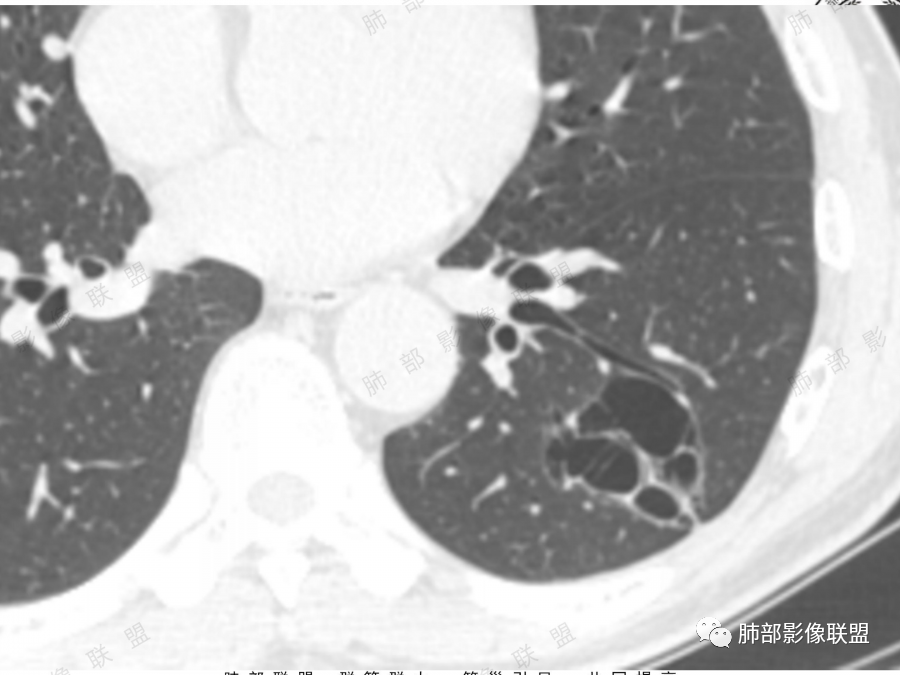

左肺下叶空腔,分隔状,壁厚薄不均,支气管截断,部分周围可见磨玻璃影,胸膜牵拉,左肺上叶多发结节,部分可见钙化,考虑1左肺下叶囊腔型腺癌。2左肺上叶结核。

中年男性,多发空腔,腔内可见分隔、壁结节。考虑:囊腔型腺癌。肺结核为陈旧性。

男51,体检发现肺部阴影,左肺下叶见多发薄壁囊腔影,可见结节,囊腔内见分隔,轻度胸膜牵拉,病灶周围少许磨玻璃影,常规考虑囊腔型腺癌,肿瘤标志物不高,除外结核。

中年男性,体检发现,吸烟史,但肺气肿背景不明显。左肺下叶囊腔病变,有一定张力,分隔明显,似有多个囊腔融合感,部分边缘见少许磨玻璃影,有支气管截断,首选囊腔型肺癌,某些先天病变(囊腺瘤样畸形等)也要考虑。

肺结核背景,左下肺簿壁囊腔,内有分格,有支气管截断,囊壁局限性增厚,嗜烟史,考虑左下囊腔型肺癌(鳞癌)。

左肺上叶陈旧肺结核,以增殖钙化灶为主,左肺上叶多发囊泡样结节,有分隔,稍分叶,周围少许磨玻璃,支气管部分截断,部分贴边穿过,老年男性,考虑囊腔型腺癌。

左肺上叶多发小结节影,部分钙化,考虑结核。左肺下叶多个囊状影,腔内见血管影,间隔稍粗大,考虑囊腔型肺癌,

老年,51岁男性病人,左上肺斑点,小结节状阴影,可见钙化,陈旧性肺结核改变,患者有长期的吸烟病史。左肺下叶背段多个囊腔肿块影,整体呈团块状类圆型,无明显壁结节,整体病灶张力较大,具备一定的膨胀感 ,支气管拉直并有突然截断改变,考虑囊腔型鳞癌。鉴别诊断:结核性病变,局限性囊性支气管扩张

男性,体检发现左肺阴影。影像表现:左上肺多发结节伴纤维条索影,部分钙化,左下肺囊腔样改变,内有分隔,部分分隔边缘见实性成分及GGO样改变,支气管从旁边经过,或受压,无明确进入依据。初步诊断:1、左上肺结核。2、左下肺囊腔型腺癌,诊断依据:分隔样囊腔,部分分隔有实变,边缘有GGO改变,鉴别诊断:1、囊腺瘤样畸形,分隔样囊腔要考虑,但部分分隔实变,部分伴GGO样改变成疑,最大的疑问是年龄51岁,体检发现,抽烟、饮酒30年,却无发病,可能性太小。2、囊腔性转移,单发分隔样囊腔转移少见,且需要病史支持。3、囊性淋巴瘤,一般以单发囊腔多见,分隔样囊腔型淋巴瘤罕见。4、感染,无相关临床症状及辅检支持,基本排除。

@傅昌瑜—贺州市人民医院—呼内 里面的血管进一步支持恶性。但不鉴别腺癌和鳞癌,主要鉴别的,还是多囊,张力较高,囊壁较薄(实变区除外),加GGO。